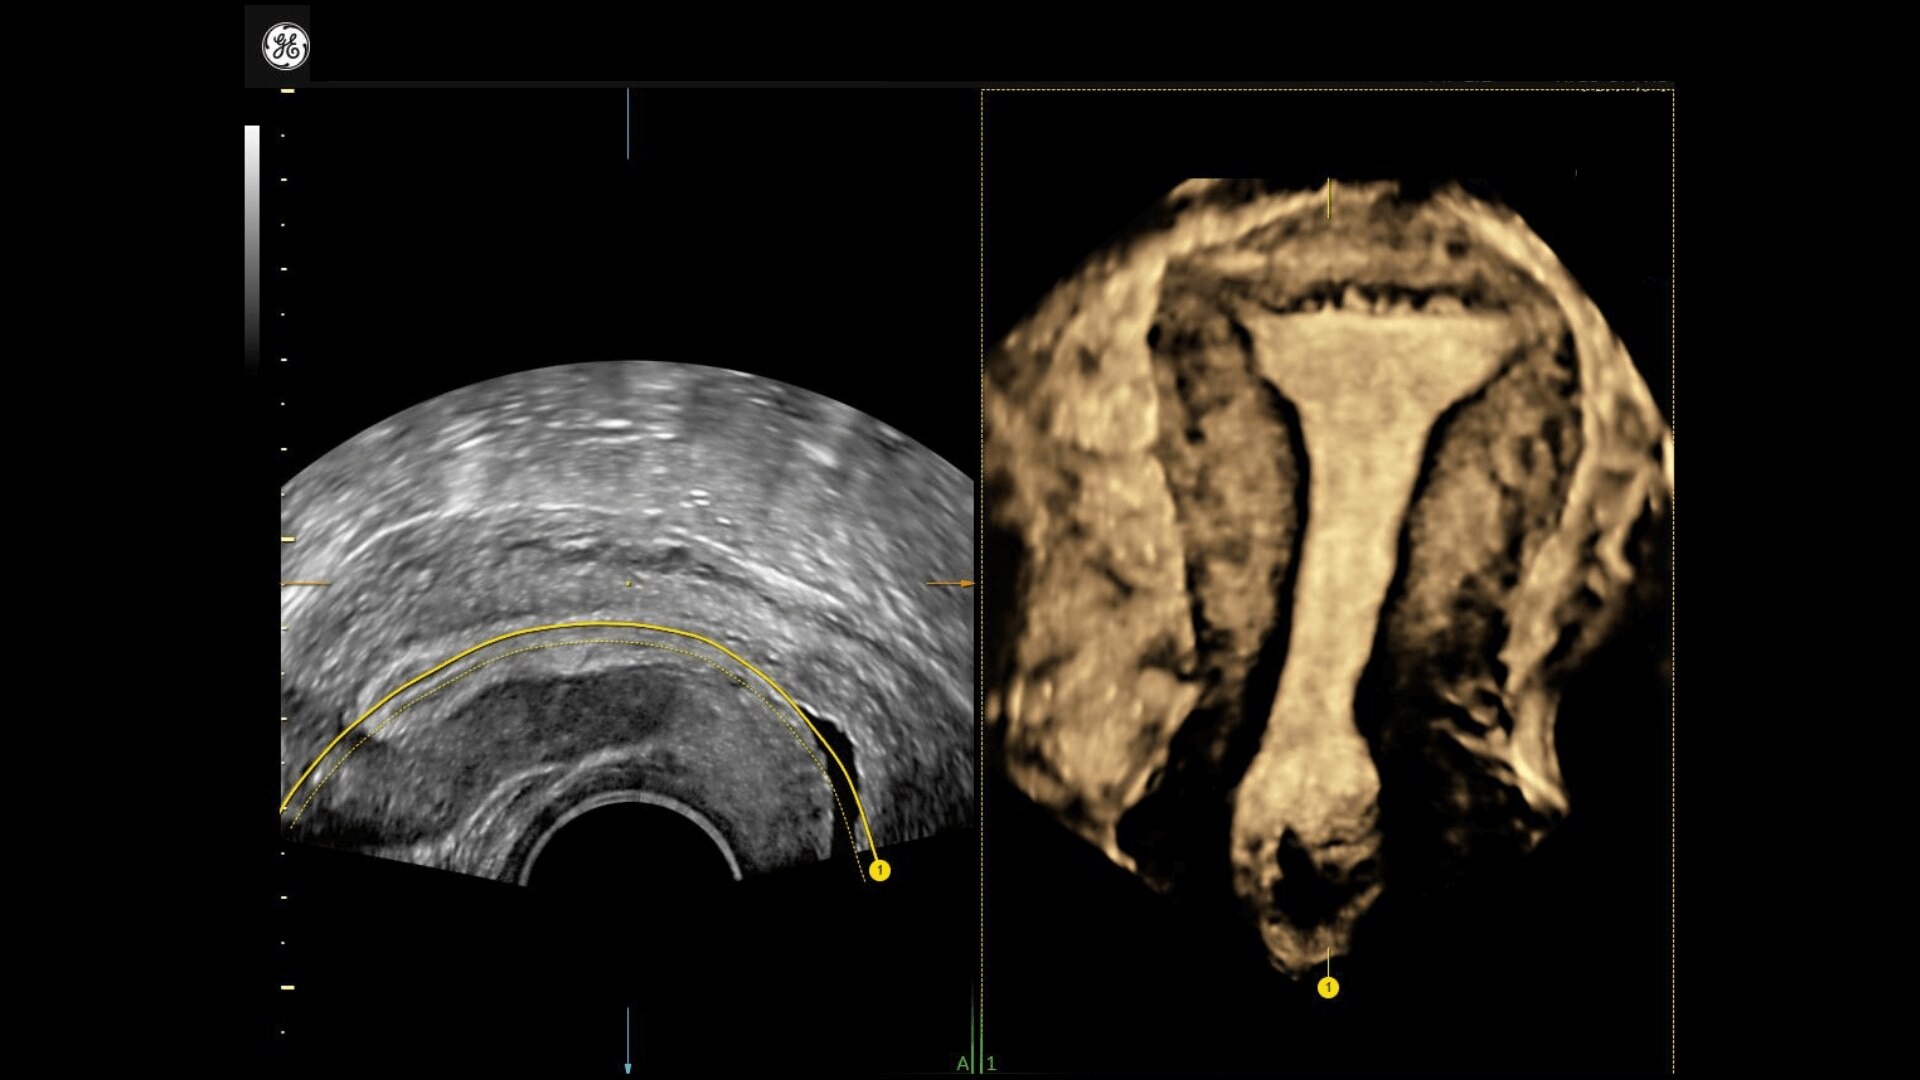

Uterine Trace

Easy display coronal view of uterus.

• Uterine Trace acquires the volume & then displays the coronal view of the uterus to simplify identification & reporting of uterine malformations.

• Uterine Trace acquires the volume and then displays the coronal view of the uterus linking to ASRM, ESHRE and ESGE Uterine Classification guidelines to simplify identification and reporting of uterine malformations